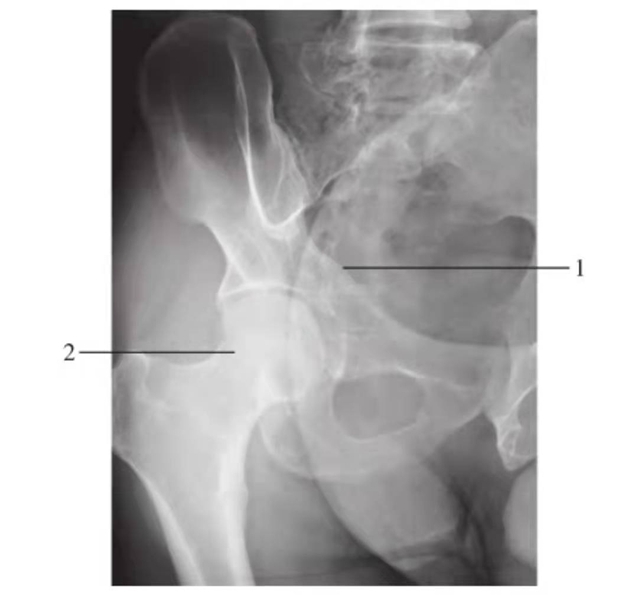

髋关节和股骨颈侧位

图3 髋关节和股骨颈侧位

1.髋臼;2.股骨头;3.股骨颈;4.大转子;5.小转子

髋关节后前斜位

图5 髋关节后前斜位(谢氏位)

1.髂骨;2.关节间隙;3.股骨头;4.股骨颈;5.大转子